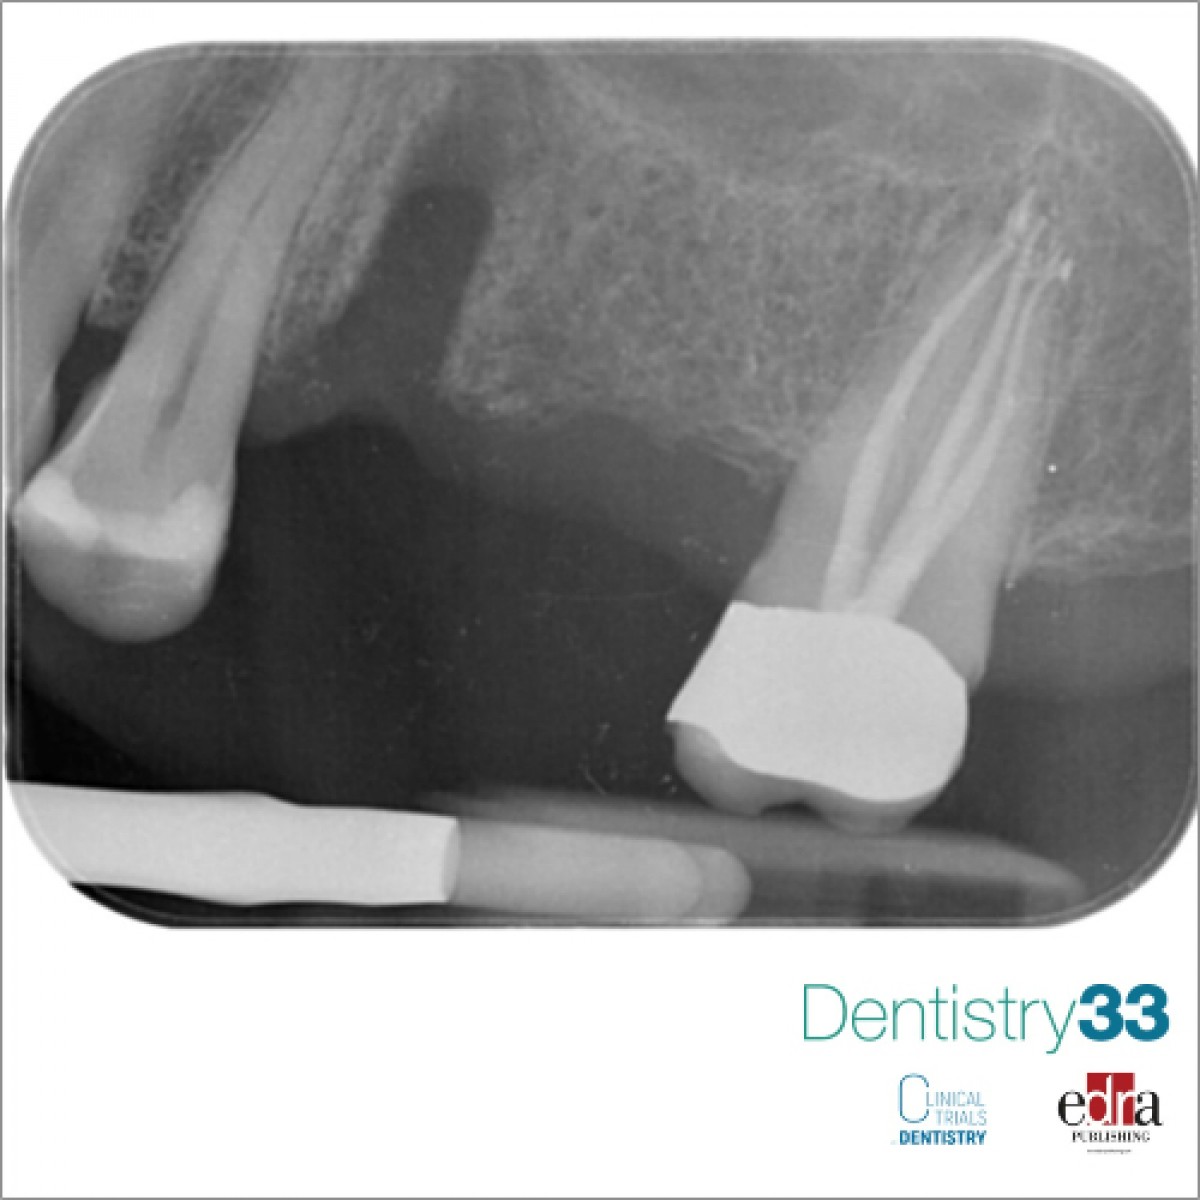

The tomographic cuts obtained (Fig. 6 and Fig. 7) allowed the accurate evaluation of the residual bone volumes and the adjacent anatomical structures not otherwise appreciable in the two-dimensional view of the site, allowing the operator to insert the implants in complete safety and full compliance of the patient's anatomy (Fig. 8)

First of 3 clinical cases in which three-dimensional radiology has allowed us to avoid making diagnostic errors otherwise not evaluable with two-dimensional radiography alone.